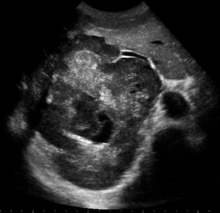

| left lobe liver tumor in 50-year-old man operated in King Saud Medical Complex, Riyadh, Saudi Arabia | |

Liver tumors or hepatic tumors are tumors or growths on or in the liver (medical terms pertaining to the liver often start in hepato- or hepatic from the Greek word for liver, hepar). Several distinct types of tumors can develop in the liver because the liver is made up of various cell types. These growths can be benign or malignant (cancerous). They may be discovered on medical imaging (even for a different reason than the cancer itself), or may be present in patients as an abdominal mass, hepatomegaly, abdominal pain, jaundice, or some other liver dysfunction.